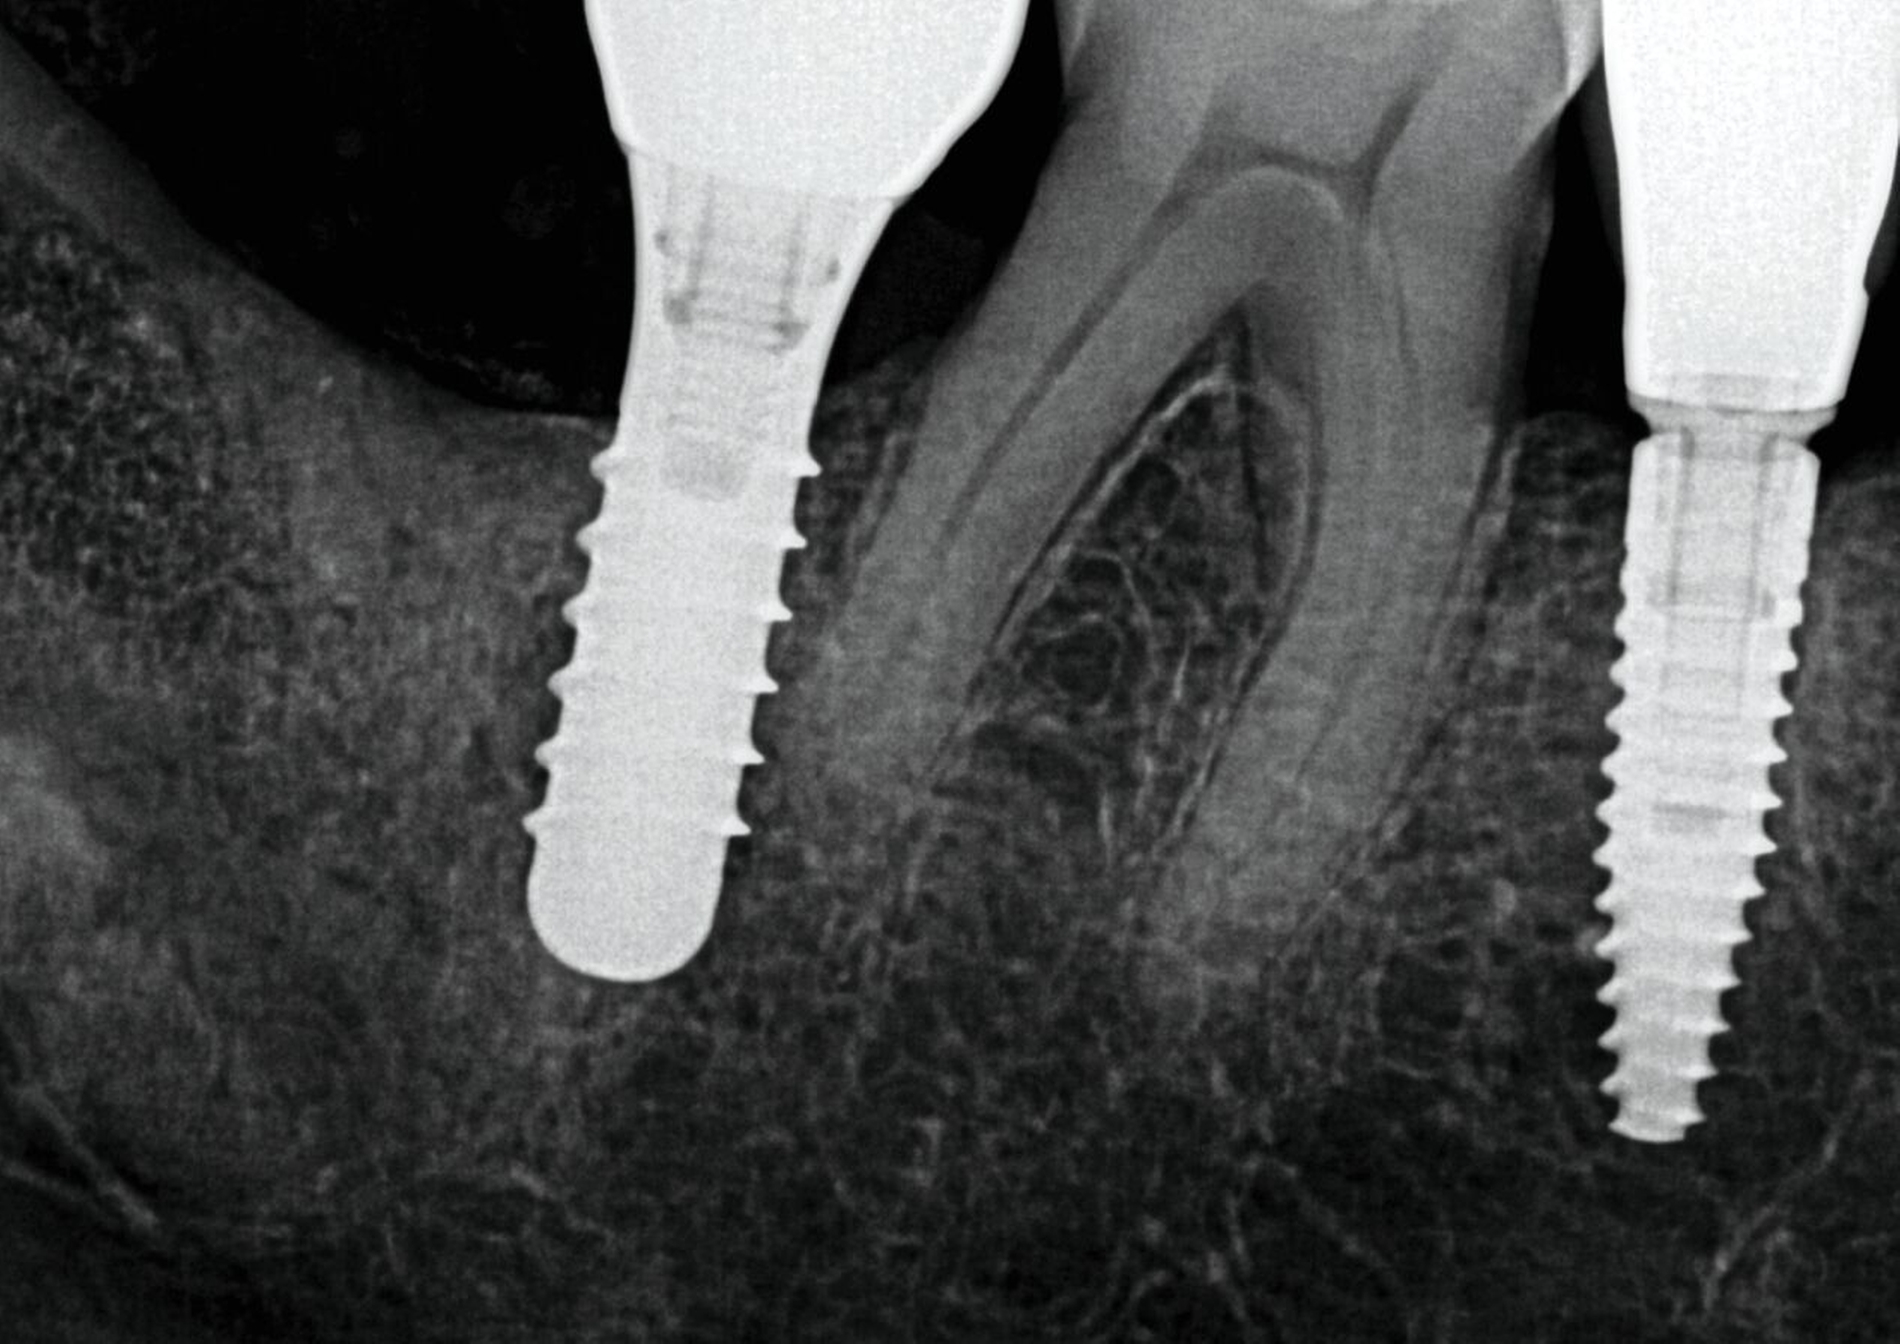

Hier kam es zum Verlust einer verschraubten Brückenkonstruktion auf einem neueren Implantatsystem (Abbildung 7). Vermutlich lag eine Kombination aus Überbelastung, unzureichender Passung, inadäquater Vorspannung oder der Verwendung nicht definitiver (zum Beispiel laborseitiger) Schrauben vor, die schließlich zum Bruch der Abutmentschrauben führte.

Glücklicherweise konnten die Schraubenfragmente im Implantat einfach entfernt werden. Mithilfe einer Wurzelkanaleingangssonde wurden sie unter dem Operationsmikroskop vorsichtig gegen den Uhrzeigersinn gedreht und ohne weiteren Schaden aus dem Implantatinneren gelöst.

Im Implantatbereich regio 35 wurde eine abgebrochene Schraube diagnostiziert. Zum Zeitpunkt der Überweisung war die Integrität der Implantatschulter bereits kompromittiert, auch die Gewindegänge wiesen deutliche Schäden auf. Obwohl das Fragment radiologisch deutlich nach koronal überstand und somit zunächst als entfernbar erschien, zeigte sich bei der mikroskopischen Kontrolle, dass es fest auf dem Boden des Implantats aufsaß. Mehrere vorsichtige Mobilisationsversuche blieben erfolglos. Aufgrund der fortgeschrittenen Schädigung wurde das Implantat schließlich mithilfe einer passgenauen Trepanfräse entfernt und durch ein neues Implantat ersetzt (Abbildung 8).